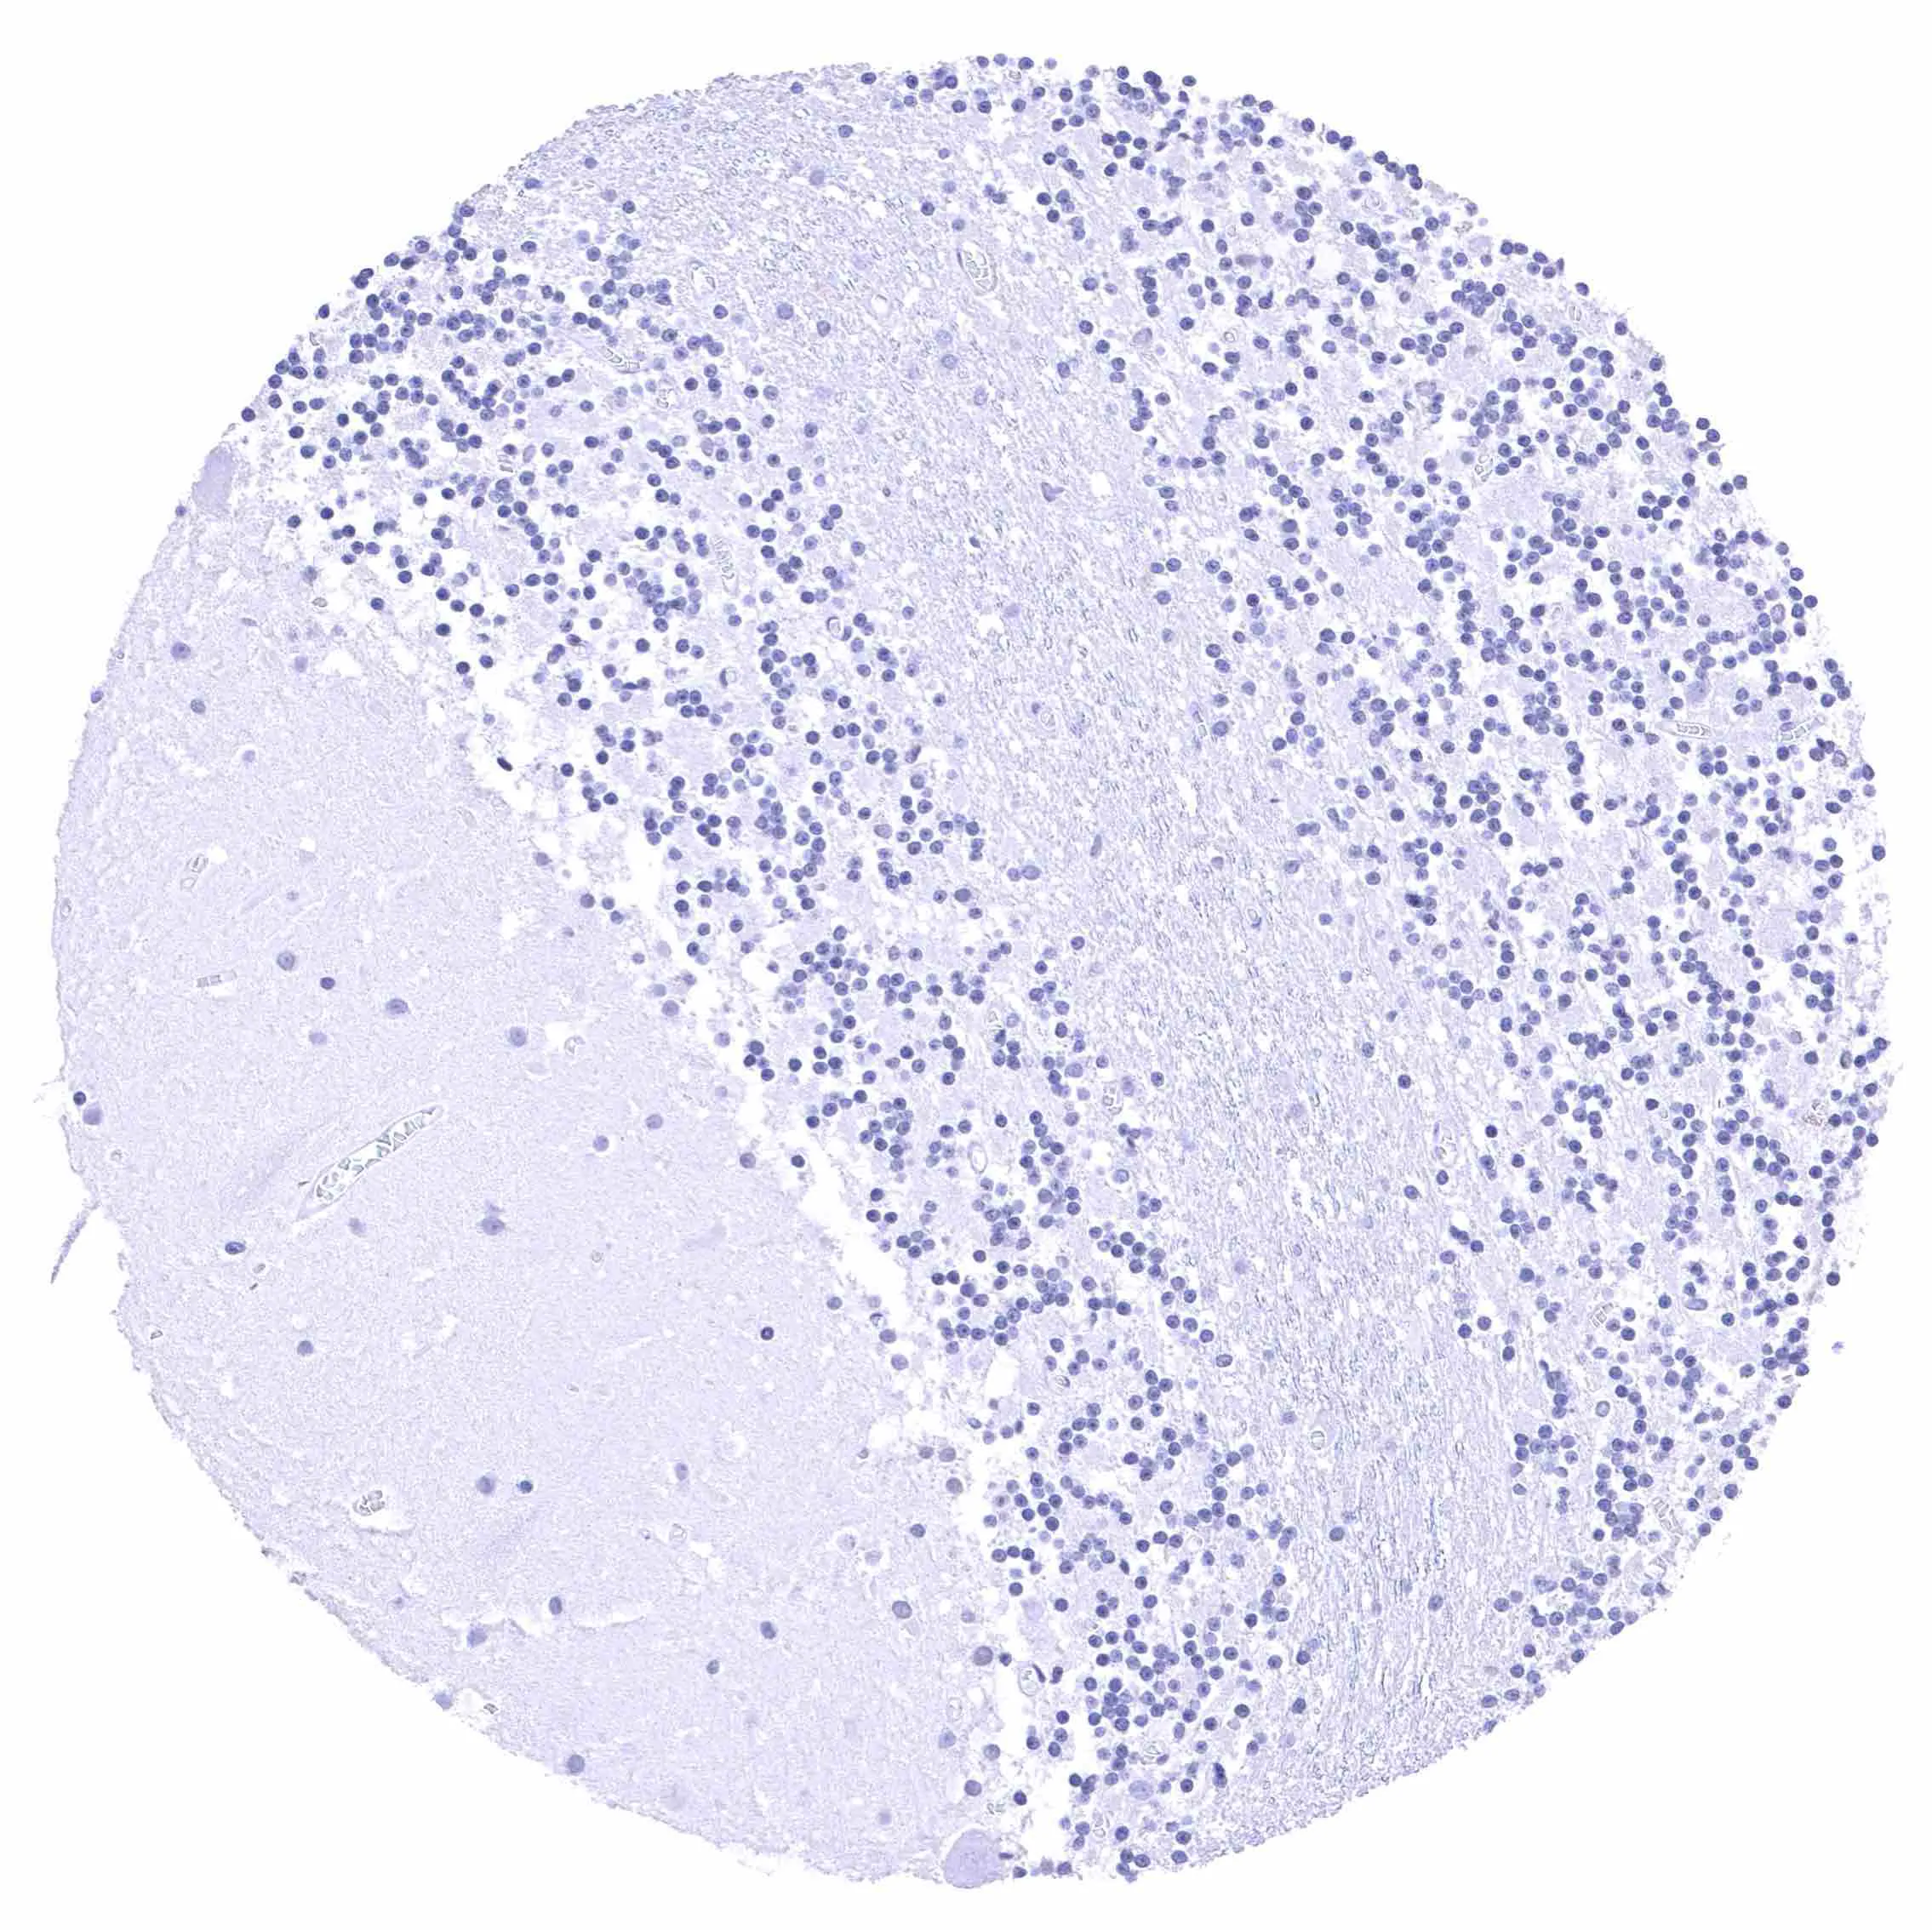

Lymph node